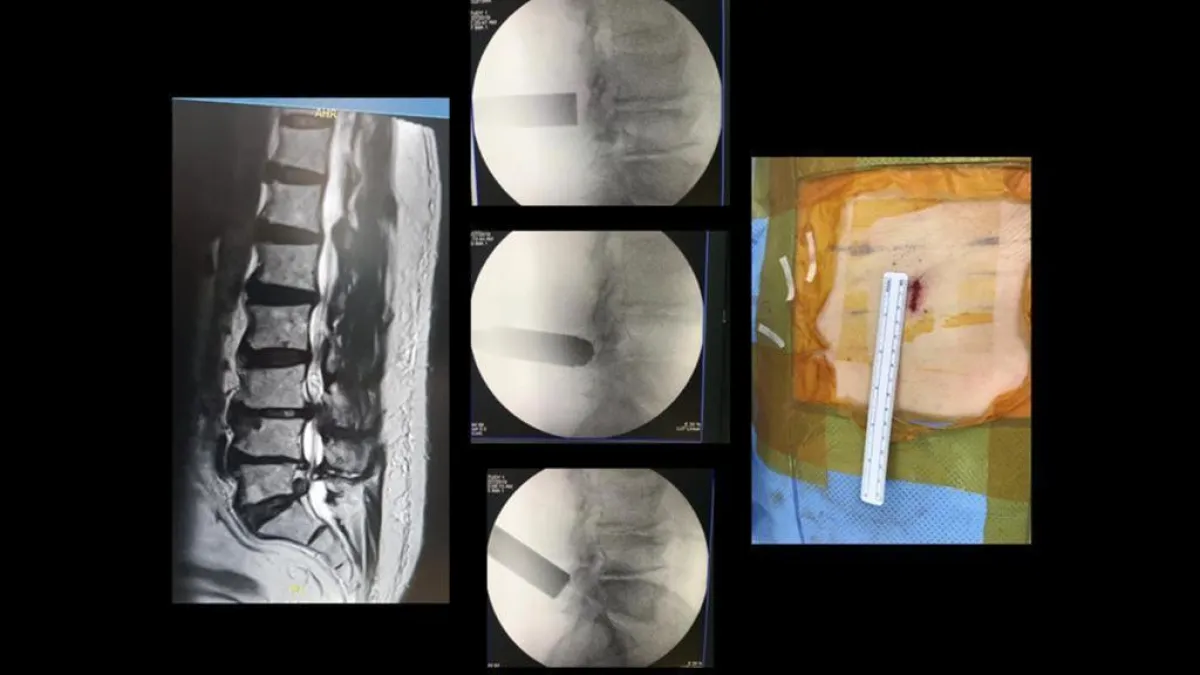

نجحت مدينة الملك عبد الله الطبية بالعاصمة المقدسة باستخدام تقنيه جديدة تمثلت في عملية إزالة الغضروف القطني وتوسيع القنوات العصبية المركزية بتقنية المنظار ولأول مرة بإجراء عشر عمليات تكللت بالنجاح.

وأوضح استشاري جراحة العمود الفقري والمشرف على هذه التقنية الدكتور أيمن رضا طيب بأن تقنية المنظار ليست حديثة العهد حيث أنه يعمل بها عالميا منذ أكثر من ثلاثين سنة وهي في تطور مستمر ومتوفرة بأشكال مختلفة تستخدم على حسب نوع المشكلة الضاغطة على الأعصاب مما تتيح نهجا جديدا للتداخل الجراحي بأقل قدر ممكن من الشق الجراحي منأاجل تنفيذ إجراءات تخفيف الضغط الناتجة عن الغضروف أو عن أي نتوءات عظمية.

وأشار إلى أنه يمكن استخدامه لعدة مستويات من الفقرات القطنية قد تصل إلى 3 مستويات من خلال شق جراحي واحد ولا يتجاوز 1.8 سم مضيفاً إلى أن هذا النوع من العمليات ذو الشق الجراحي المحدود تقلل من احتياج المريض للأدوية المسكنة ما بعد العملية وبالتالي مكوث المريض في المستشفى يكون أقل مع سرعه التعافي بإذن الله.